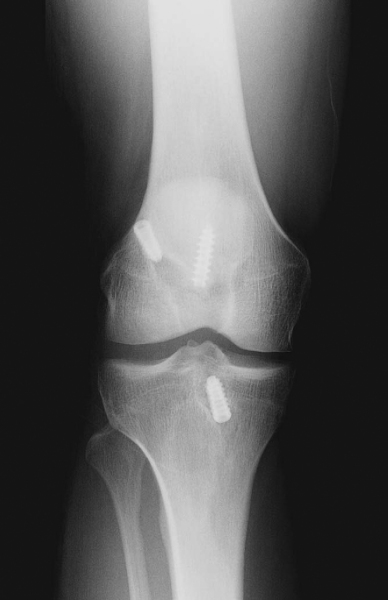

It is critical to consider whether former hardware will require removal or whether it may be bypassed at revision surgery. A variety of interference screws are commercially available with differing morphologic appearances radiographically. Most can be removed with a standard 3.5-mm screwdriver, although a screw manufactured by Instrument Makar (Okemos, Mich) requires a threaded extractor. If previous tunnels are nonanatomic and nonoverlapping, the hardware can generally be left in place (Figs. 64-3 and 64-4 [3] [4]). If the tunnels will overlap, the hardware may require initial removal for the new tunnel to be made, but it may have to be subsequently reinserted to provide construct fixation stability. In our experience, bioabsorbable screws are generally not resorbed at the time of revision surgery and frequently fracture on attempted removal secondary to softening. The surgeon may therefore have to ream through these screws to properly position the new tunnel.

The ideal location for the femoral tunnel is in the 1-o’clock (left knees) or 11-o’clock (right knees) position with 1 to 2 mm of intact posterior wall. Careful inspection of the previous tunnel is performed; if it is in the correct location, it can be reused. However, if it is positioned too anterior, a new tunnel is drilled behind it (see

Fig. 64-3A

). In this case, we recommend keeping the old hardware in place to act as an anterior buttress. On occasion, a deficient posterior wall precludes interference screw fixation with the endoscopic technique, in which case a two-incision technique can be used to secure the ACL on the anterior femur instead.